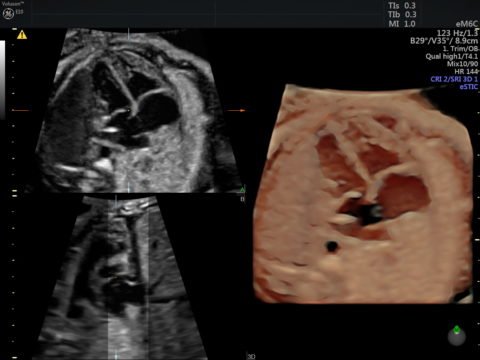

A magzat szíve szűrés szempontjából a legbonyolultabb szerv, még akkor is ha élettani állapotot mutat. A lehetséges szívfejlődési rendellenességek sokasága, illetve ezek kombinációja nehéz feladat elé állítja a vizsgálót. A kiterjesztett magzati echocardiographia során olyan extra síkok vizsgálatára is sor kerül, mellyekkel tovább növelhető a szívfejlődési rendellenességek felismerése – 50%-ról a szenzitivitás 90%-ra emelhető.

Amennyiben valamilyen szívhibát látunk vagy annak gyanúja merül fel, további gyermekkardiológus által végzett kivizsgálás és tanácsadás javasolt annak megítélésére, hogy a magzat megszületése után milyen kimenetelre lehet számítani illetve milyen eséllyel gyógyítható az észlelt szívrendellenesség.